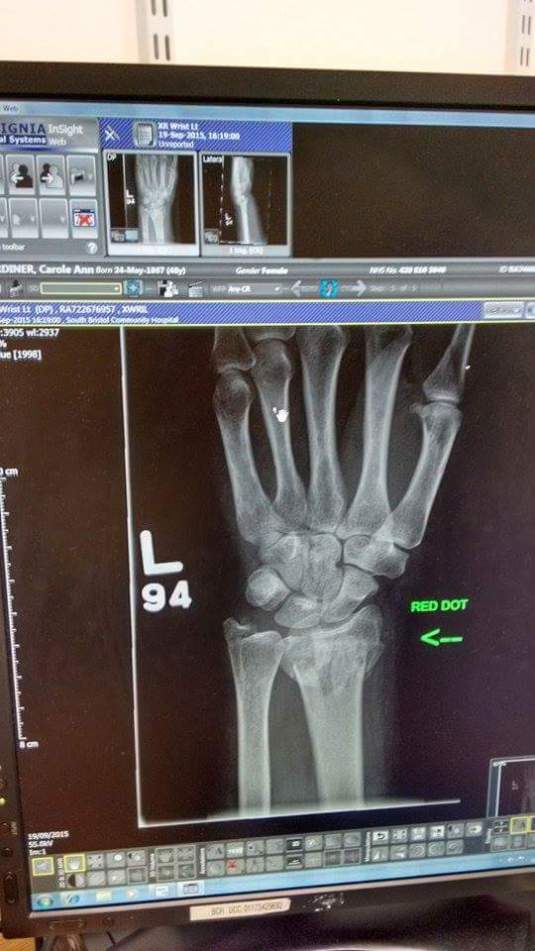

After a lengthy wait in the Emergency Department an xray revealed a displaced Collies fracture of my distal radius causing 2 fractures on both sides of my ulna. In other words I made a right mess of my wrist and as it was in the shape of a Z, it needed to be pulled back into a straight line under local anaesthetic. I spent 6 painful weeks in plaster and have been going to physio ever since.